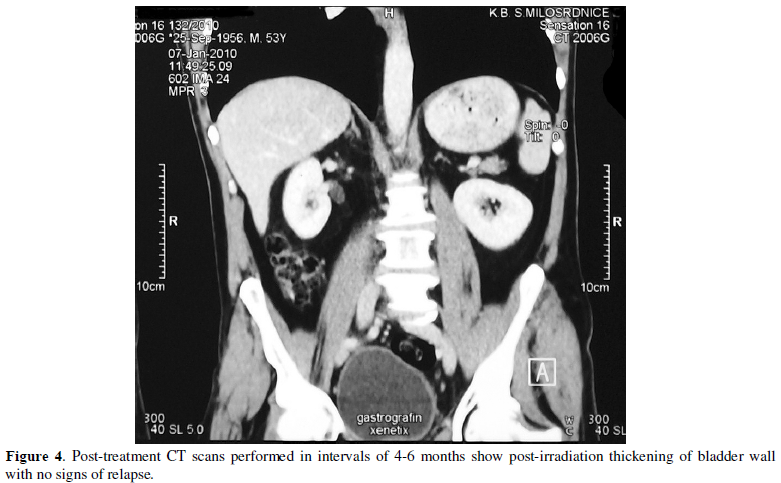

the patient with adjuvant chemotherapy and radiotherapy. Six months postoperatively pelvic CT scan (Figure

4) and cystoscopy were unremarkable.